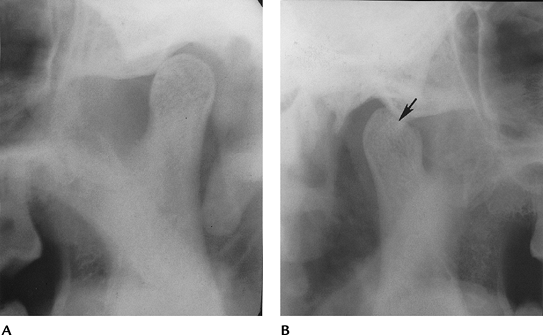

![]() |

FIGURE 2-4 (A) Sagittal spin-echo 500/10 image does not clearly identify the disc. (B) Coronal spin-echo 500/10 image shows lateral displacement (arrows).

Anterior and anterolateral displacements account for 46% to 52% of disc displacements.

-

Rotational displacement was associated with 34% of displacements that did not reduce with opening and 53% of reducing discs.

Additional categories of internal

derangement include 11% with partial displacement, 4% with stuck discs

(disc does not move with condylar motion), and 1% with posterior

displacements. -

MRI is 95% accurate for disc position and classification and 93% accurate for osseous abnormalities.